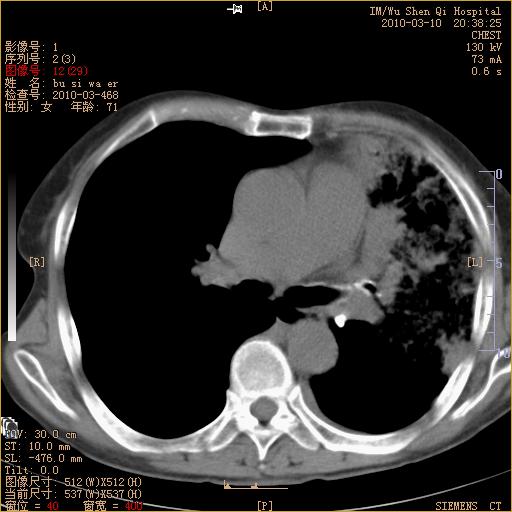

以下是引用随光逐影在2010-3-11 0:41:00的发言:[br]1)考虑左肺及右肺上叶继发性肺结核并左肺炎症感染。2)左侧支气管内膜结核可能;建议必要时行纤支镜检查。3)肺气肿。4)心包膜增厚(或少量心包积液)。5)左侧胸腔积液。